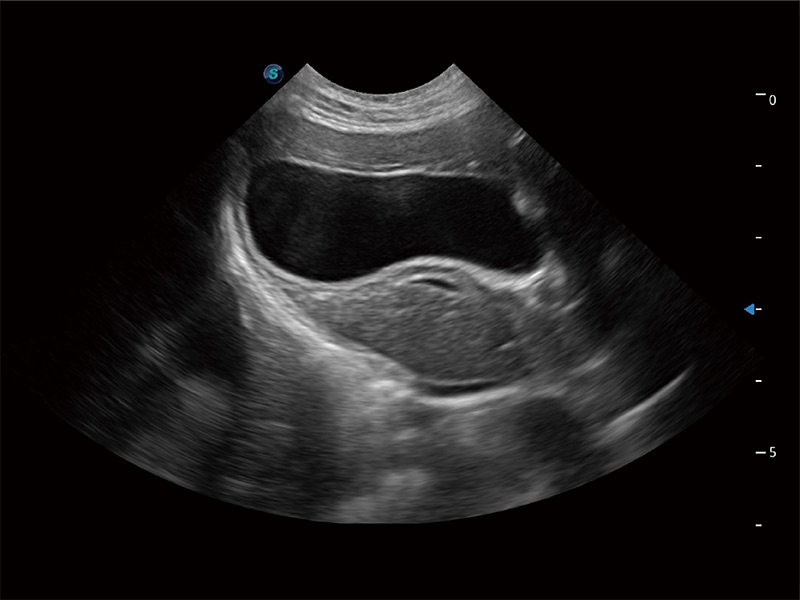

ProPet 80 配备了丰富的心脏探头群、先进的成像技术和专业的心脏测量工具,可帮助动物医生为不同体型和生理结构的动物提供心脏和心肌功能的全面评估。

ProPet 80 专为动物医生设计,对不同的动物体型和生理结构作出了针对性的优化。通过动物影像专用软件,可满足个性化的应用需求,帮助动物医生获得更精确的诊断数据。

ProPet 80 全新的动物超声智能软件和丰富的探头群,为动物医生提供了高清晰度和精细分辨率的图像,无论在宠物、马科、畜牧还是实验室动物等应用中都可以轻松应对,为您的日常工作带来满意的体验。